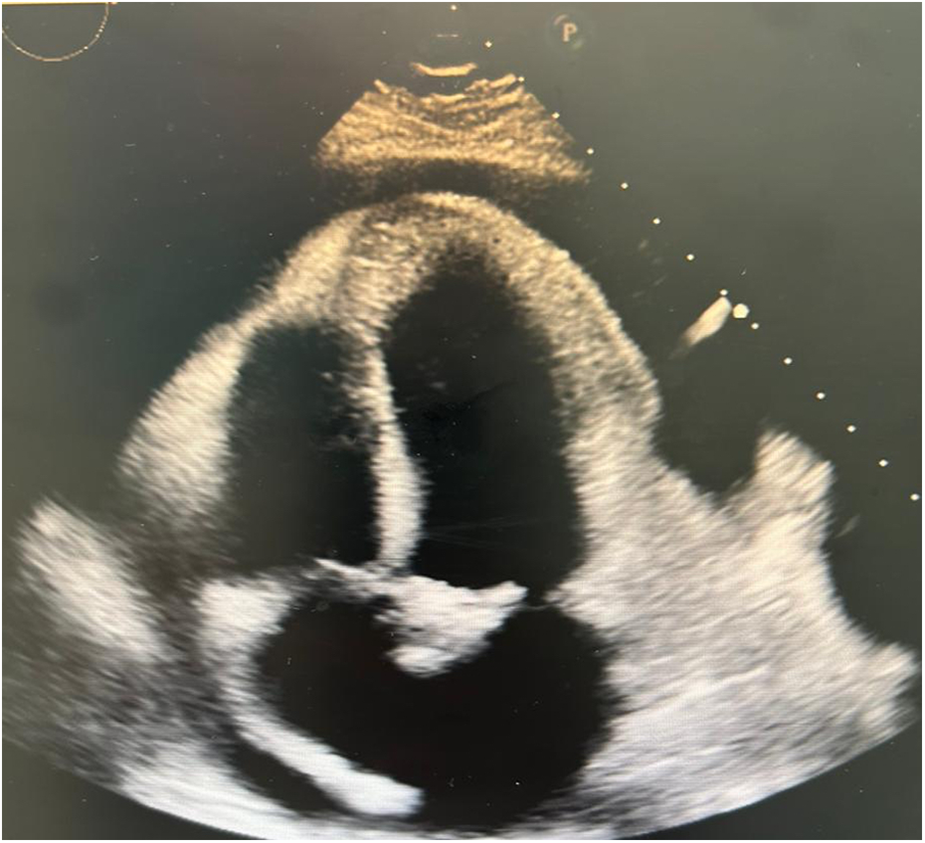

Figure 2

Echocardiogram 2D showing pericardial effusion, no signs of tamponade.

The electrocardiogram showed sinus tachycardia (Figure 1) and chest x-ray demonstrated mediastinal widening. Laboratory results are shown in Table 1. The echocardiographic study showed a left ventricular ejection fraction of 65%, mitral E wave velocity of 134 cm/s, and mitral A wave velocity of 121 cm/s. E/e': 20. Mild calcified aortic valve stenosis and severe pericardial effusion without signs of tamponade (Figure 2).

Echocardiography may be normal in acute pericarditis but is essential to demonstrate pericardial effusion and to semi-quantitatively describe its size in diastole as trivial (systolic only), mild (<10 mm), moderate (10–20 mm), severe (21–25 mm), and very severe (>25 mm) (6). Additionally, it allows assessment of hemodynamic compromise and signs of cardiac tamponade through a Doppler study of mitral and tricuspid flow velocities (change of >30%–40% suggestive of tamponade) (7). In or case, echocardiography was crucial for diagnosing pericardial effusion and to initiate management, although the mentioned Doppler study was not performed.